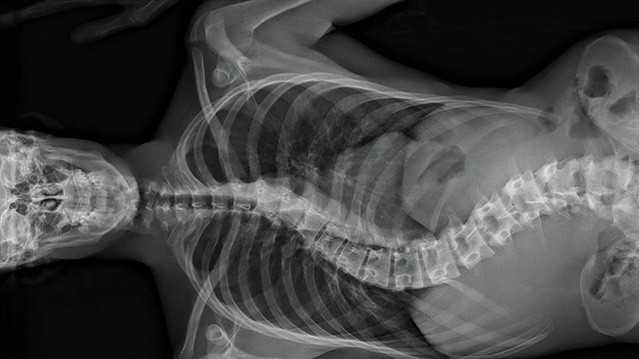

解剖学发明以来,人体奥秘开始为世人所知所见。然而,大家习惯的始终是那副最表面的臭皮囊,或留恋或厌倦,或拥抱或憎恶。假如能深入体腔,即时观察微肌细理,体液流动,可会了悟个中奥妙,那欲肉不为肉所欲的真义?得到医院前线及技术人员协助,韦莲娜柏丽芙与路西安卡斯当泰来再现了内窥和 微创手术的影像,辅以病人和医护的生活点滴,让作为关怀、痛苦、希望和被宰制场所的身体,成了光影景观的主角。血肉不再模糊的结果,可会对人文多一份凝视?